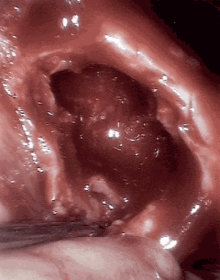

An open cavitation.

Cavitation, in biology, is the formation of cavities in an organ, especially in lung tissue as a result of tuberculosis. It can also be caused by squamous cell lung carcinoma after necrosis of the central part.[1]